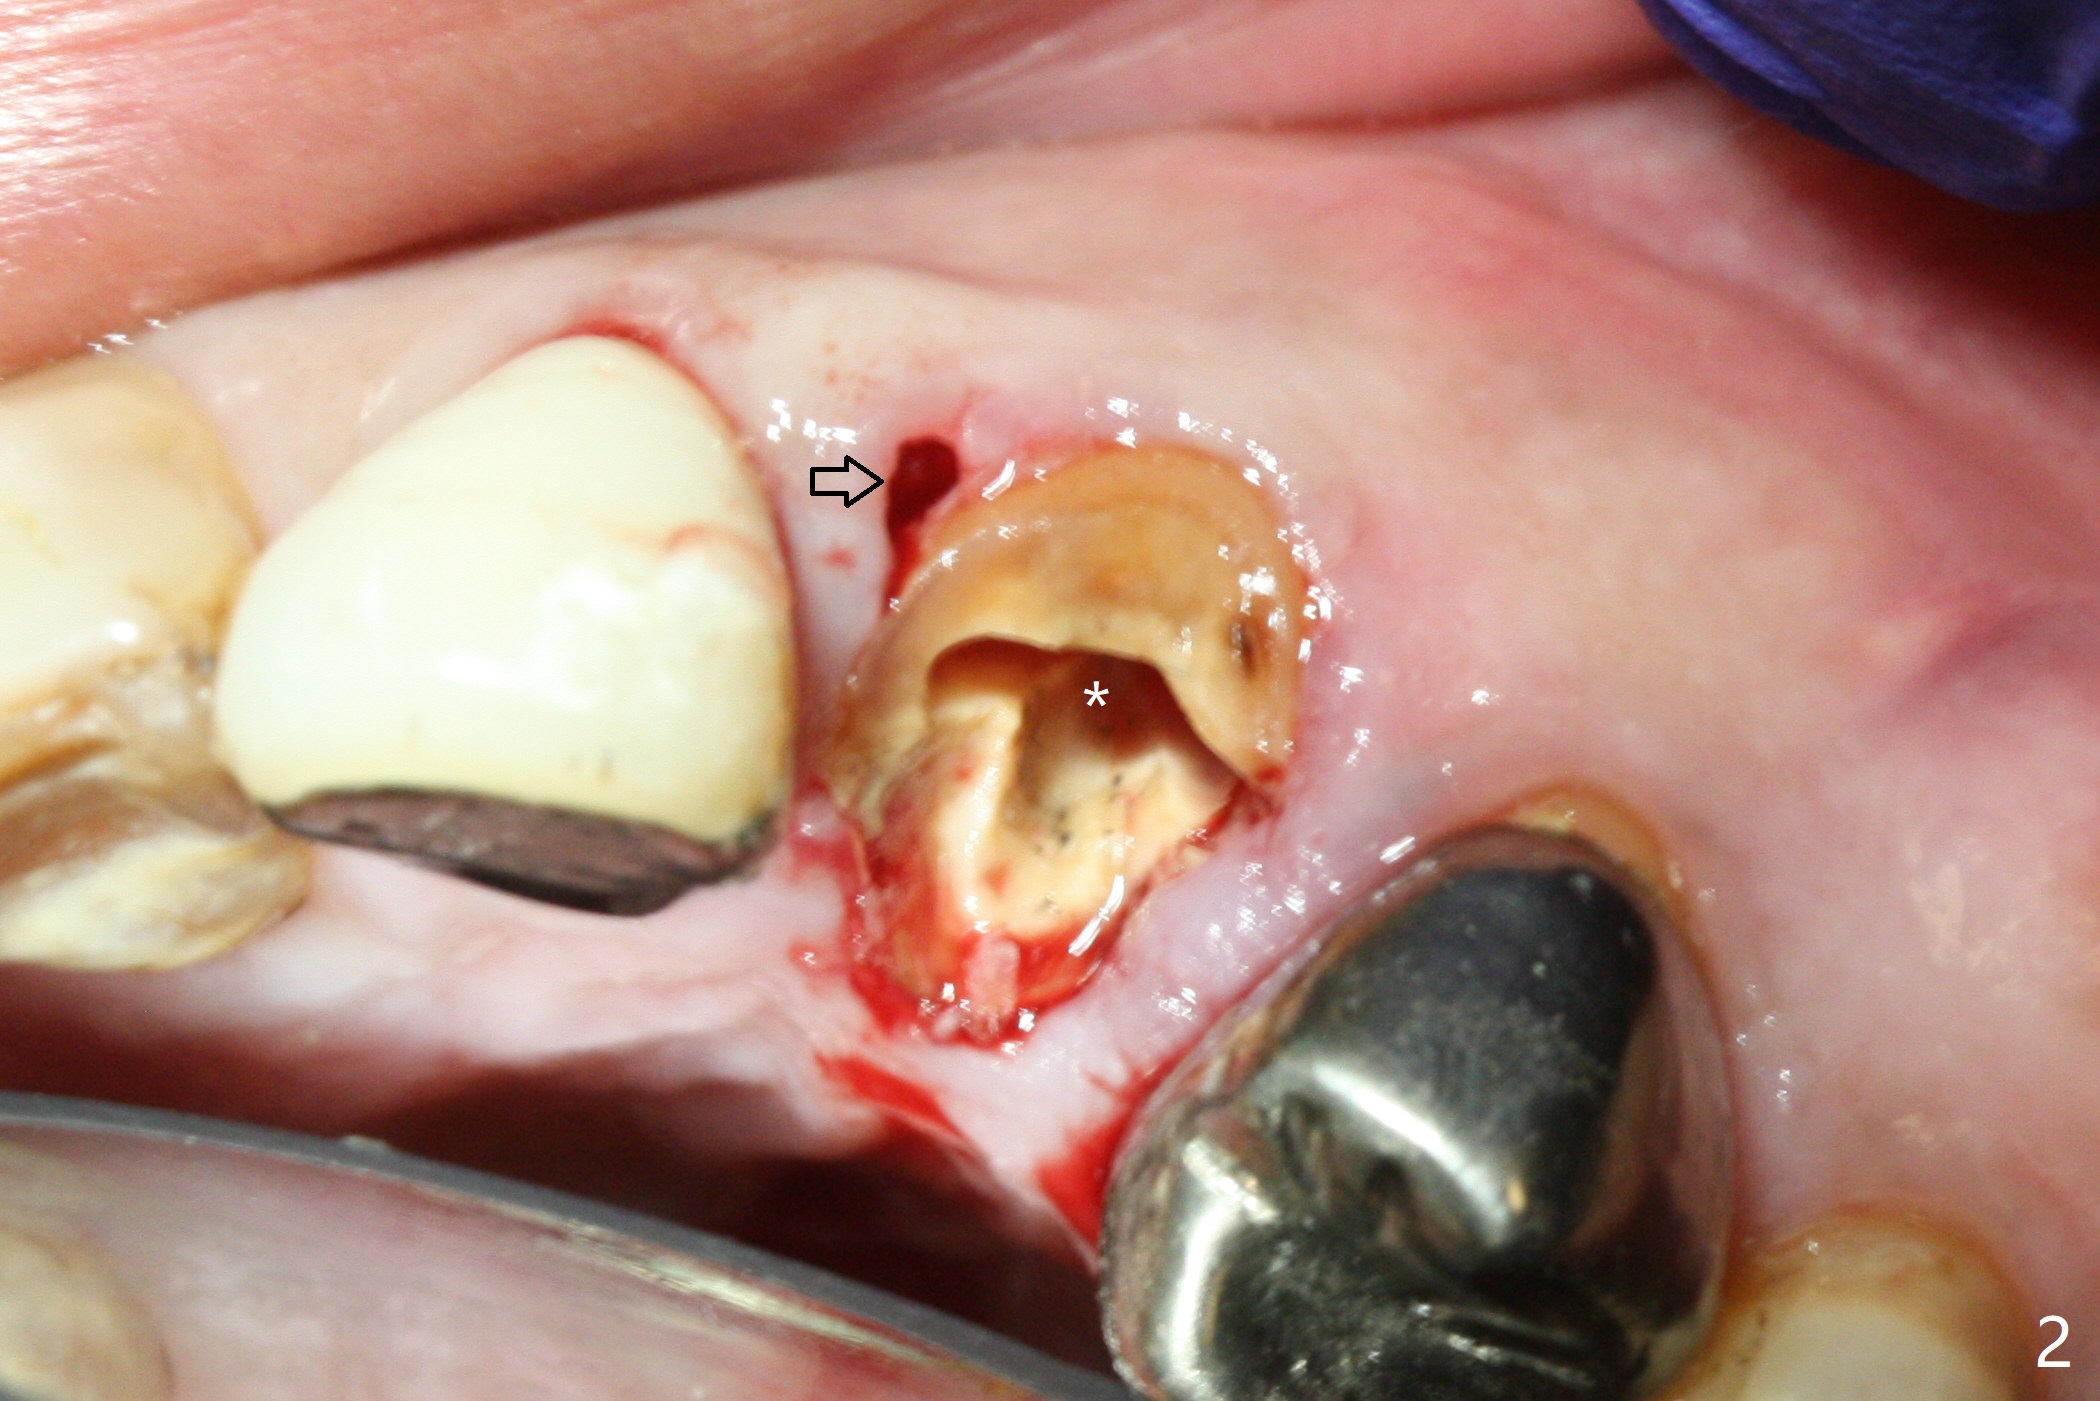

Extraction of the residual root at #11 (Fig.1) turns out to be difficult (Fig.2 (arrow: after use of small elevator). The tooth is sectioned (Fig.2 *); the palatal portion is removed, while the buccal one is trimmed until new moon-shaped and subgingival (Fig.3 * (gauze (G) packed in the socket while photo taking)). Initial osteotomy is 20 mm deep with nasal floor perforation (Fig.4). The subsequent depth is 17 mm (Fig.5). When a 5x17 mm tissue-level implant is placed (Fig.6,7; >60 Ncm), there is a gap between it and the socket shield (Fig.6 *). Gap-filling Vera Graft (Fig.8 *) also covers the shield prior to fabrication of an immediate provisional (Fig.9). There is no apparent bone loss 3.5 months postop (Fig.10). There is no buccal plate resorption 9 months postop (Fig.11). The implant is doing well 2 years postop (1 year 9 months post cementation, Fig.12).